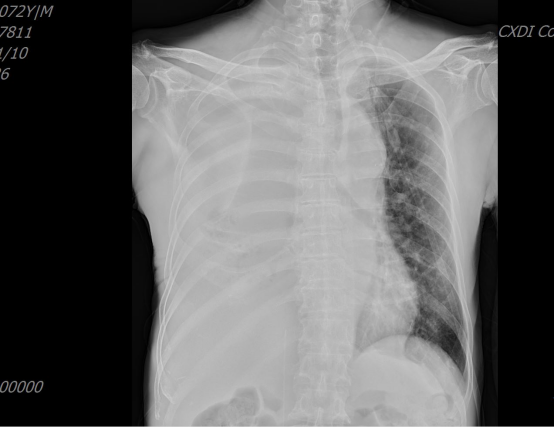

胸片(术前):右肺上叶中央型肺癌并右肺中下叶阻塞性肺不张

胸片(术后):右中下肺叶复张